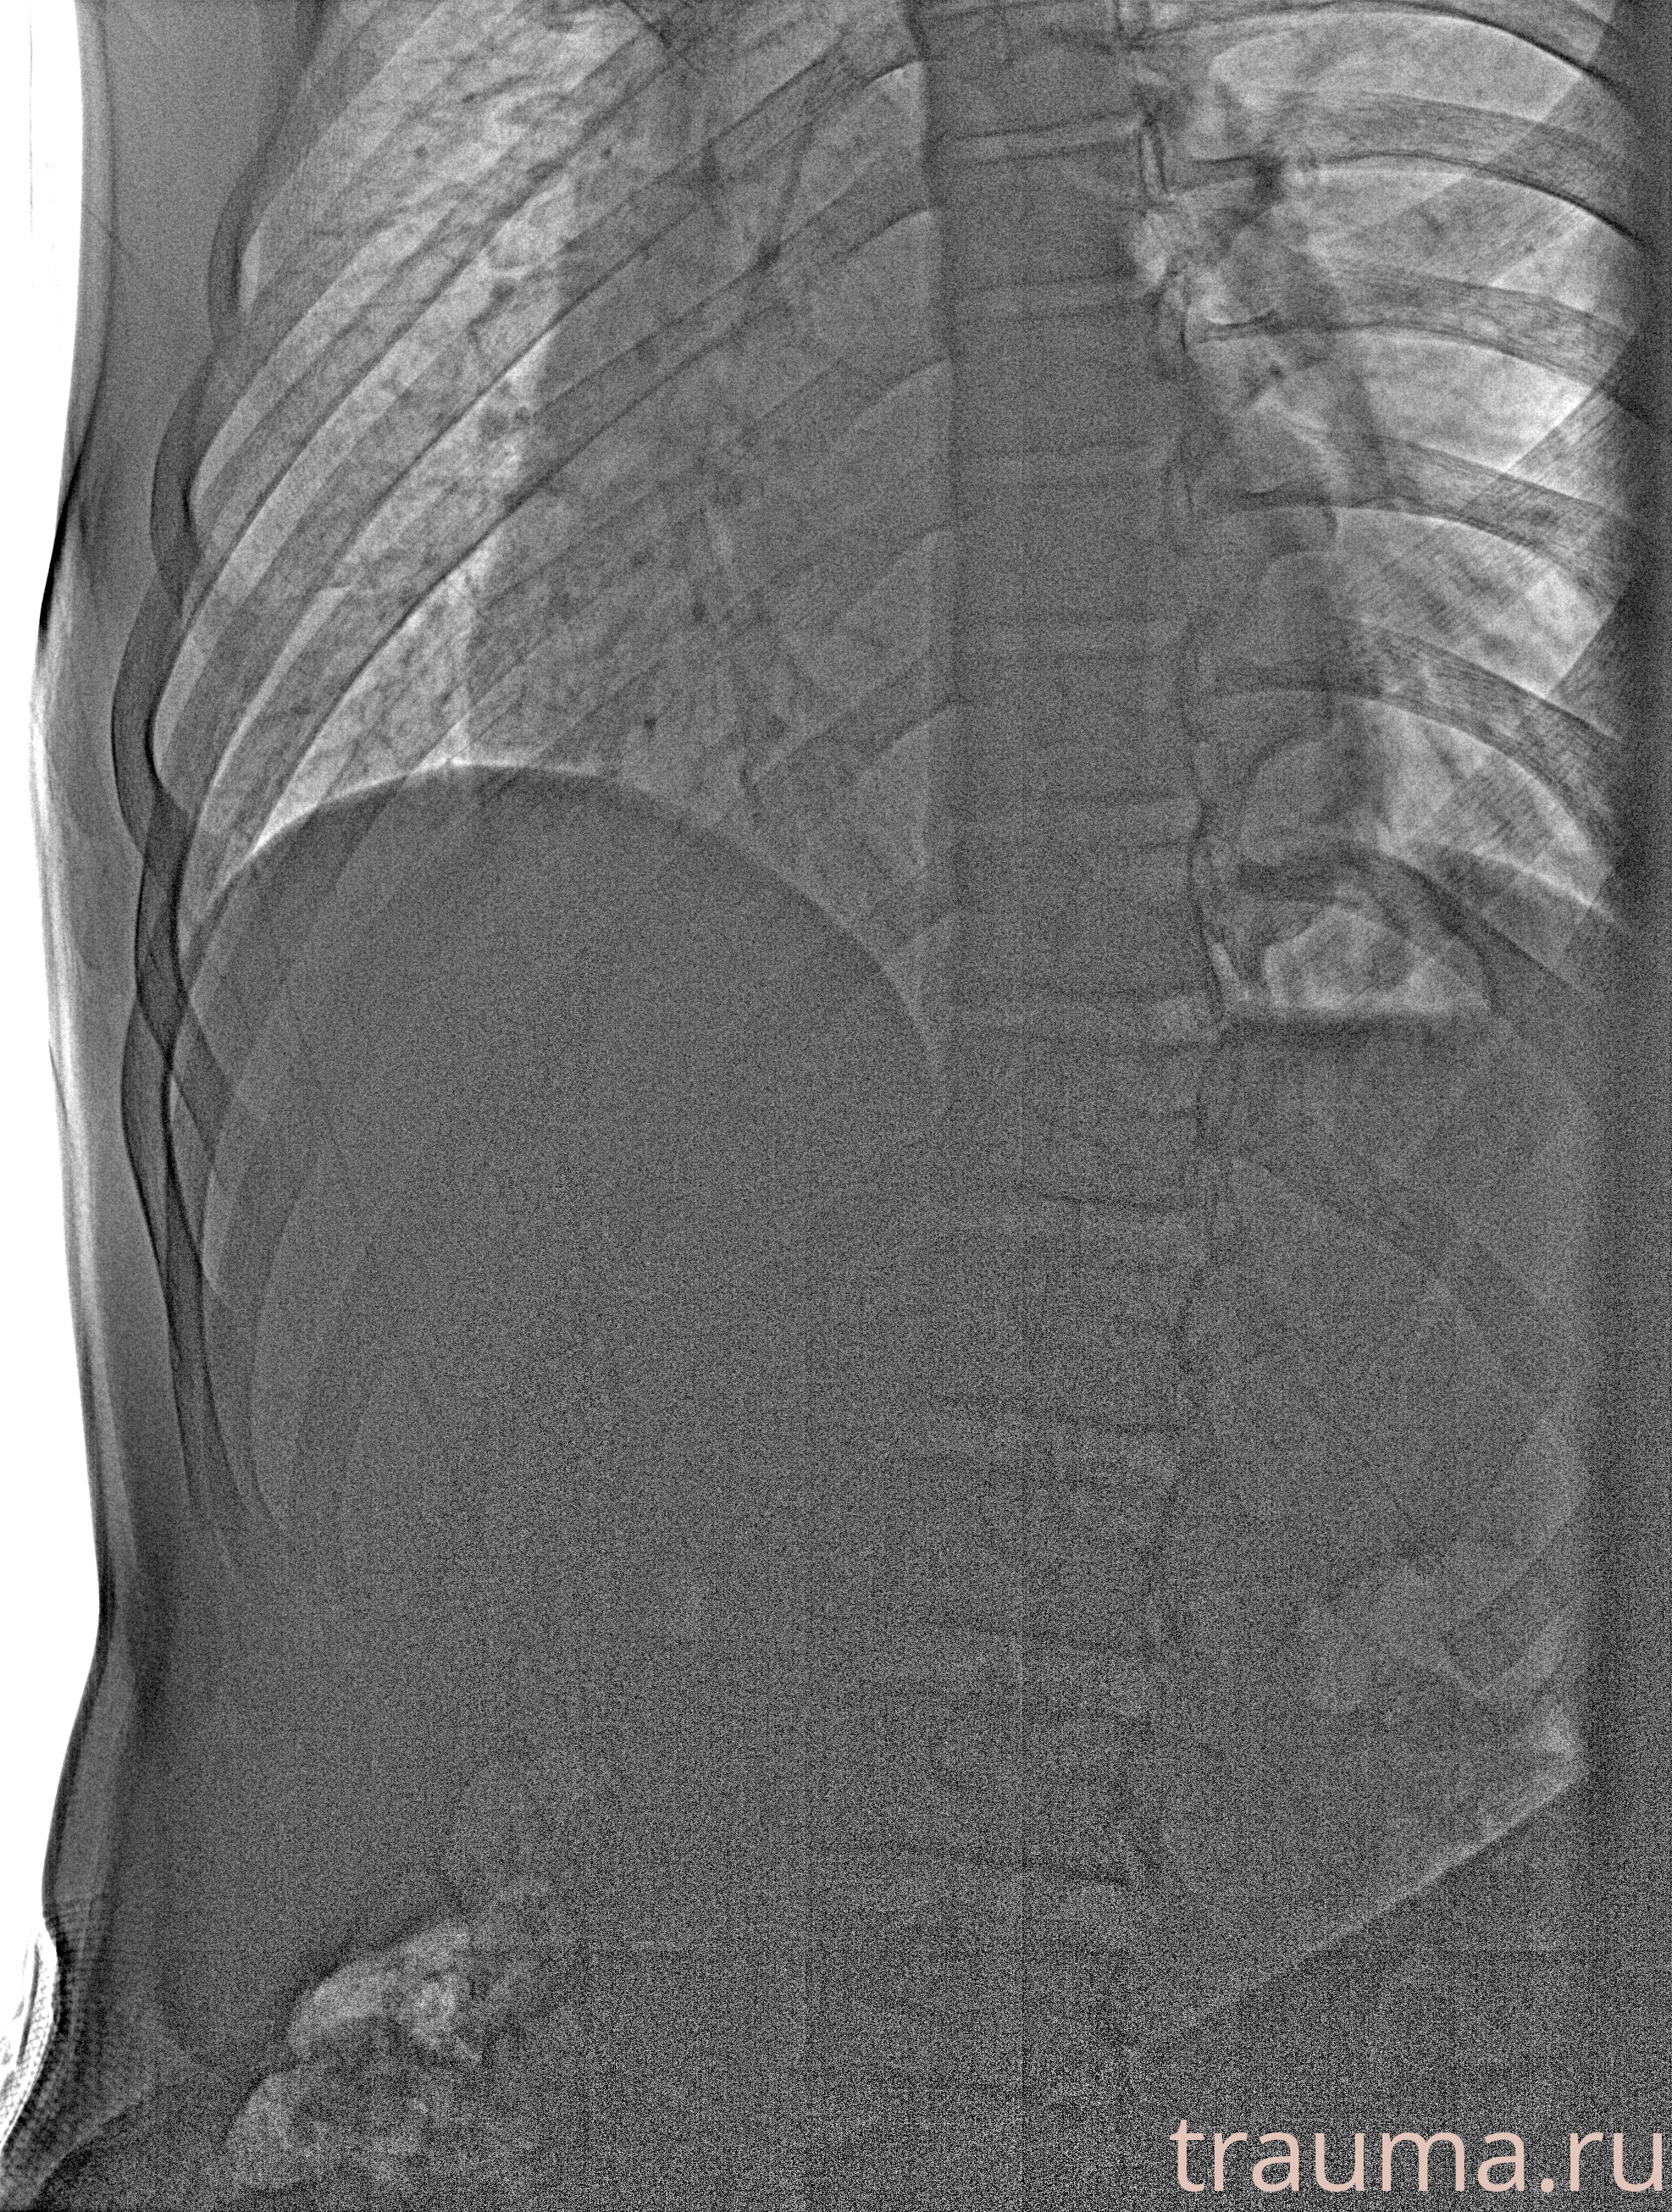

Рентген на дому: по вашему адресу приезжает врач-рентгенолог, травматолог-ортопед с мобильным рентгеновским аппаратом, проводит диагностику травмы или заболевания, делает необходимые рентгенограммы, дает рекомендации по дальнейшему лечению. Получить качественные снимки в домашних условиях возможно благодаря уникальной методике, разработанной МосРентген Центром для института  Склифосовского